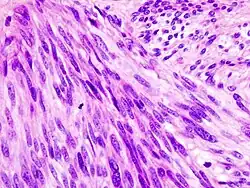

Histopathologic image of gastrointestinal stromal tumor of the stomach. Hematoxylin-eosin stain.

The definitive diagnosis is made with a biopsy, which can be obtained endoscopically, percutaneously with CT or ultrasound guidance or at the time of surgery. A biopsy sample will be investigated under the microscope by a pathologist physician. The pathologist examines the histopathology to identify the characteristics of GISTs (spindle cells in 70-80%, epitheloid aspect in 20-30%). Smaller tumors can usually be confined to the muscularis propria layer of the intestinal wall. Large ones grow, mainly outward, from the bowel wall until the point where they outstrip their blood supply and necrose (die) on the inside, forming a cavity that may eventually come to communicate with the bowel lumen.

When GIST is suspected—as opposed to other causes for similar tumors—the pathologist can use immunohistochemistry (specific antibodies that stain the molecule CD117 [also known as c-KIT] —see below). 95% of all GISTs are CD117-positive (other possible markers include CD34, Discovered On GIST-1 (DOG1),[19] desmin, and vimentin). Other cells that show CD117 positivity are mast cells.